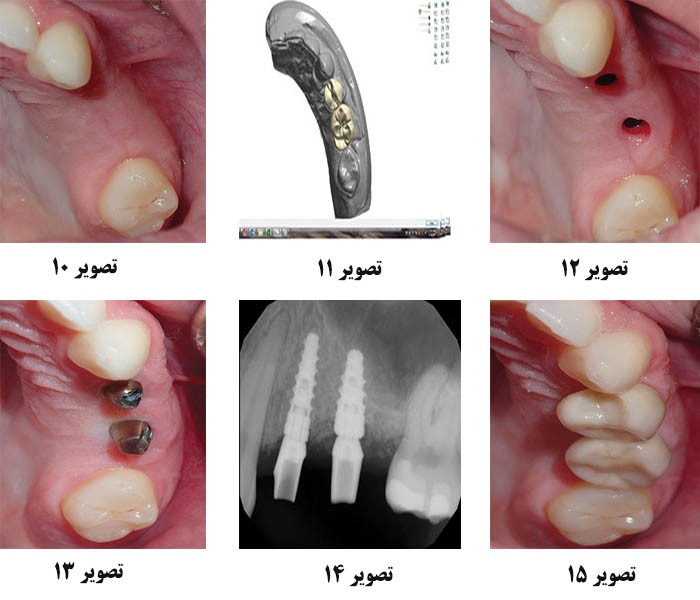

تصویر 10. 4 ماه پس از جراحی، این تصویر بسته، بهبود عرض لبه و بازسازی موفقیت آمیز استخوان و بافت نرم را نشان می دهد.

تصویر 11. ترميم هاي ايمپلنت که براي پشتيباني مطلوب به کار رفته اند با استفاده از نرم افزار CAD دنداني با دقت طراحي شده اند.

تصویر 12. پایه های درمانی برداشته شدند، که نشان می دهد بافت به خوبی شکل گرفته است که از مشخصه ی ظهور زیبایی شناختی پشتیبانی می کند.

تصویر 13. پایه های تیتانیومی (Glidewell Laboratories) قرار داده شدند، حاشیه های دقیقی ایجاد کرده و به آرامی زیر سطح لثه قرار گرفتند.

تصویر 14. جاگیری کامل پایه های سفارشی با رادیوگرافی تایید شد. به ادغام کامل Hahn Tapered Implants در گسترش لبه توجه کنید.

تصویر 15. تحویل نهایی تاج های زیرکونیوم یکپارچه (زیرکونیوم جامد کامل BruxZir [Glidewell Laboratories]) تناسب دقیقی از پایه های سفارشی ایجاد کرد.

بیمار پس از 4 ماه به منظور ارزیابی پایداری ریج و ایمپلنت بازگشت (تصویر 10). سایت با یک شکاف در تاج پوشش اش برداشته شد، و یک ریج ضخیم و سالم ایجاد کرد. ایمپلنتها دارای ثبات بالا و یکپارچگی کاملی در استخوان لبه ی گسترش یافته می باشند. پایه های بهبود دهنده ی سیستم های ایمپلنتHahn Tapered (آزمایشگاه های Glidewell) به ایمپلنت ها متصل شدند تا مشخصات ظهور زیبایی شناختی را برای ترمیم نهایی به وجود آورند، سایت نیز سپس بخیه شد.

یک ماه بعد، پستهای انتقالی به ایمپلنت متصل شده و اثرات VPS گرفته شدند. بر اساس اثرات نهایی، Glidewell Dental با استفاده از نرم افزار CAD پیشرفته دندانپزشکی، پایه های سفارشی تیتانیومی و تاج های نهایی را طراحی کرده است (تصویر 11). پایه های سفارشی برای اطمینان از قرارگیری صحیح حاشیه ای 0.5 میلی متر زیر سطح لثه طراحی شده اند. تاج های زیرکونیک یکپارچه (Zirconia[Laboratories Glidewell] BruxZir Full-Strength Solid) برای اطمینان از دوام طولانی مدت انتخاب شده است، که برای ترمیم ایمپلنت عقبی ایده آل است.

در قرار تحویل نهایی، برداشتن پایه های بهبود دهنده، شکل های سالم شیاری را در اطراف ایمپلنت های کانونی Hahn ایجاد کرد (تصویر 12). پایه های سفارشی دقیقا مطابق آناتومی بافت نرم محل های ایمپلنت جا گرفتند (تصویر 13). پس از سفت كردن پیچ پروتز، نشست كامل پایه های سفارشی با رادیوگرافی تایید شد (تصویر 14). نهایتا تاج های زیرکونیوم یکپارچه تحویل داده شدند، که با وجود ضعف ریج در زمان مشاوره اولیه، نتایج قابل پیش بینی و زیبایی شناختی ایجاد کردند (تصویر 15).